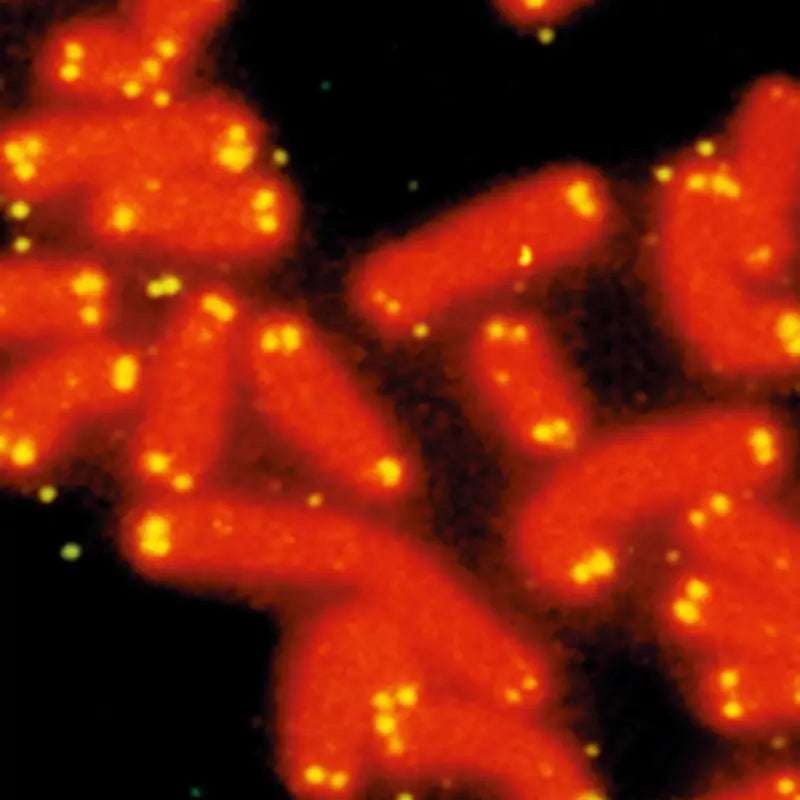

telomere shortening 12 hallmarks of aging in dogs 5

Image Credit: Dr. Robert Moyzis, UC Irvine, US Human Genome Program.

5. Telomere shortening

Telomeres are the ‘caps’ on the ends of chromosomes, the thread-like strands that contain DNA. Telomeres shorten with each round of cell replication, and a mechanism in cells controls how short telomeres can get before replication stops and cells become senescent. Unfortunately, as telomeres get shorter, DNA becomes more susceptible to damage.